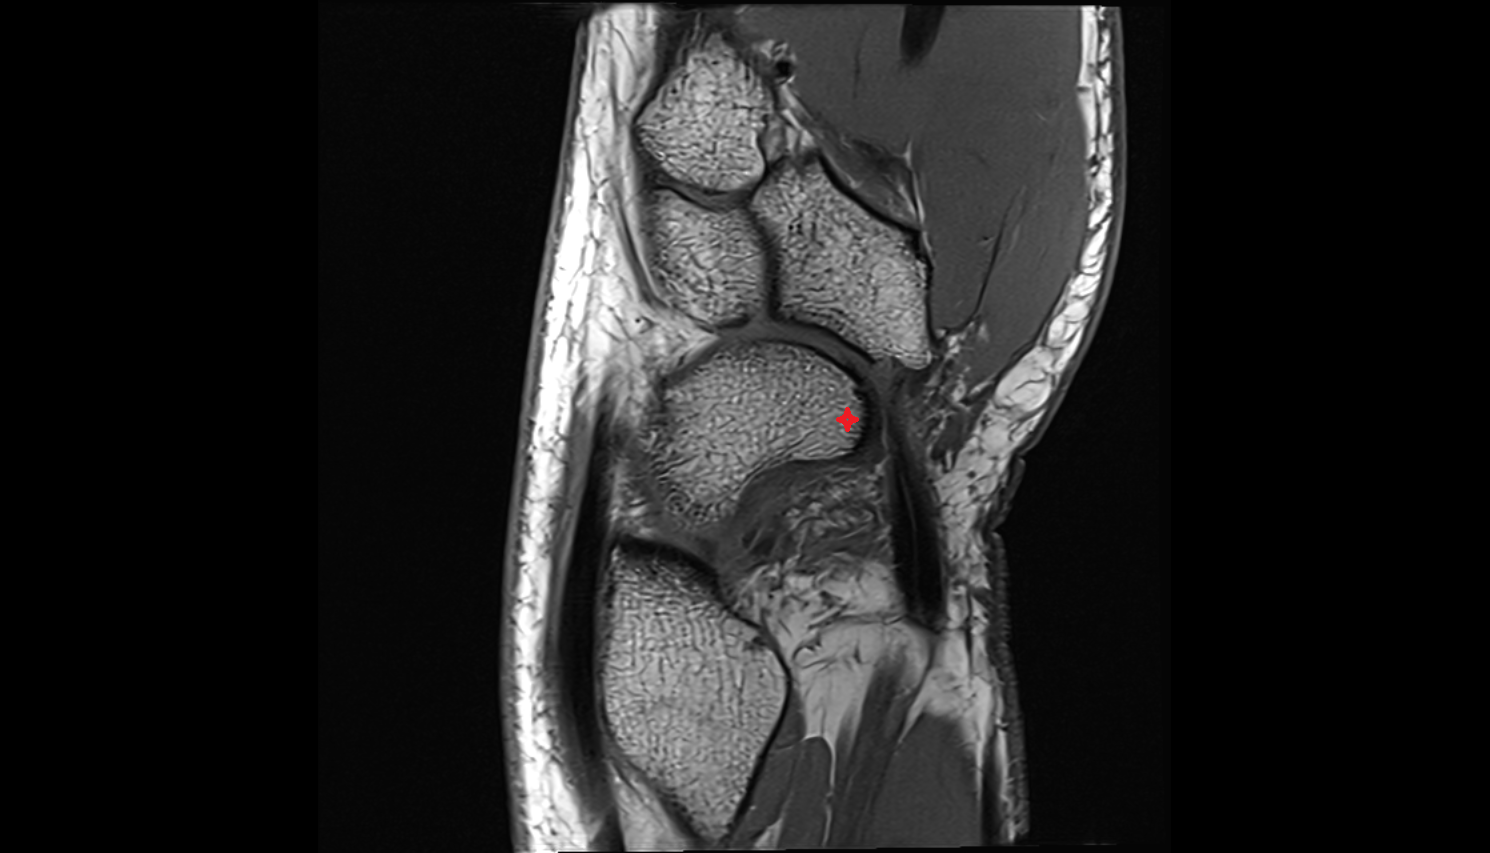

- Temporomandibular joint

- Mandibular condyle

- Mandibular fossa